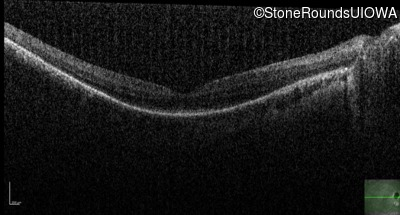

Optical Coherence Tomography - Right - 20/100 +1

Exemplar / OCT Stack

OCT Stack